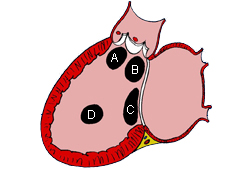

Subtipos dos defeitos do septo ventricular: (A) saída; (B) perimembranoso; (c) entrada; (D) muscular

Mayo Clinic Foundation